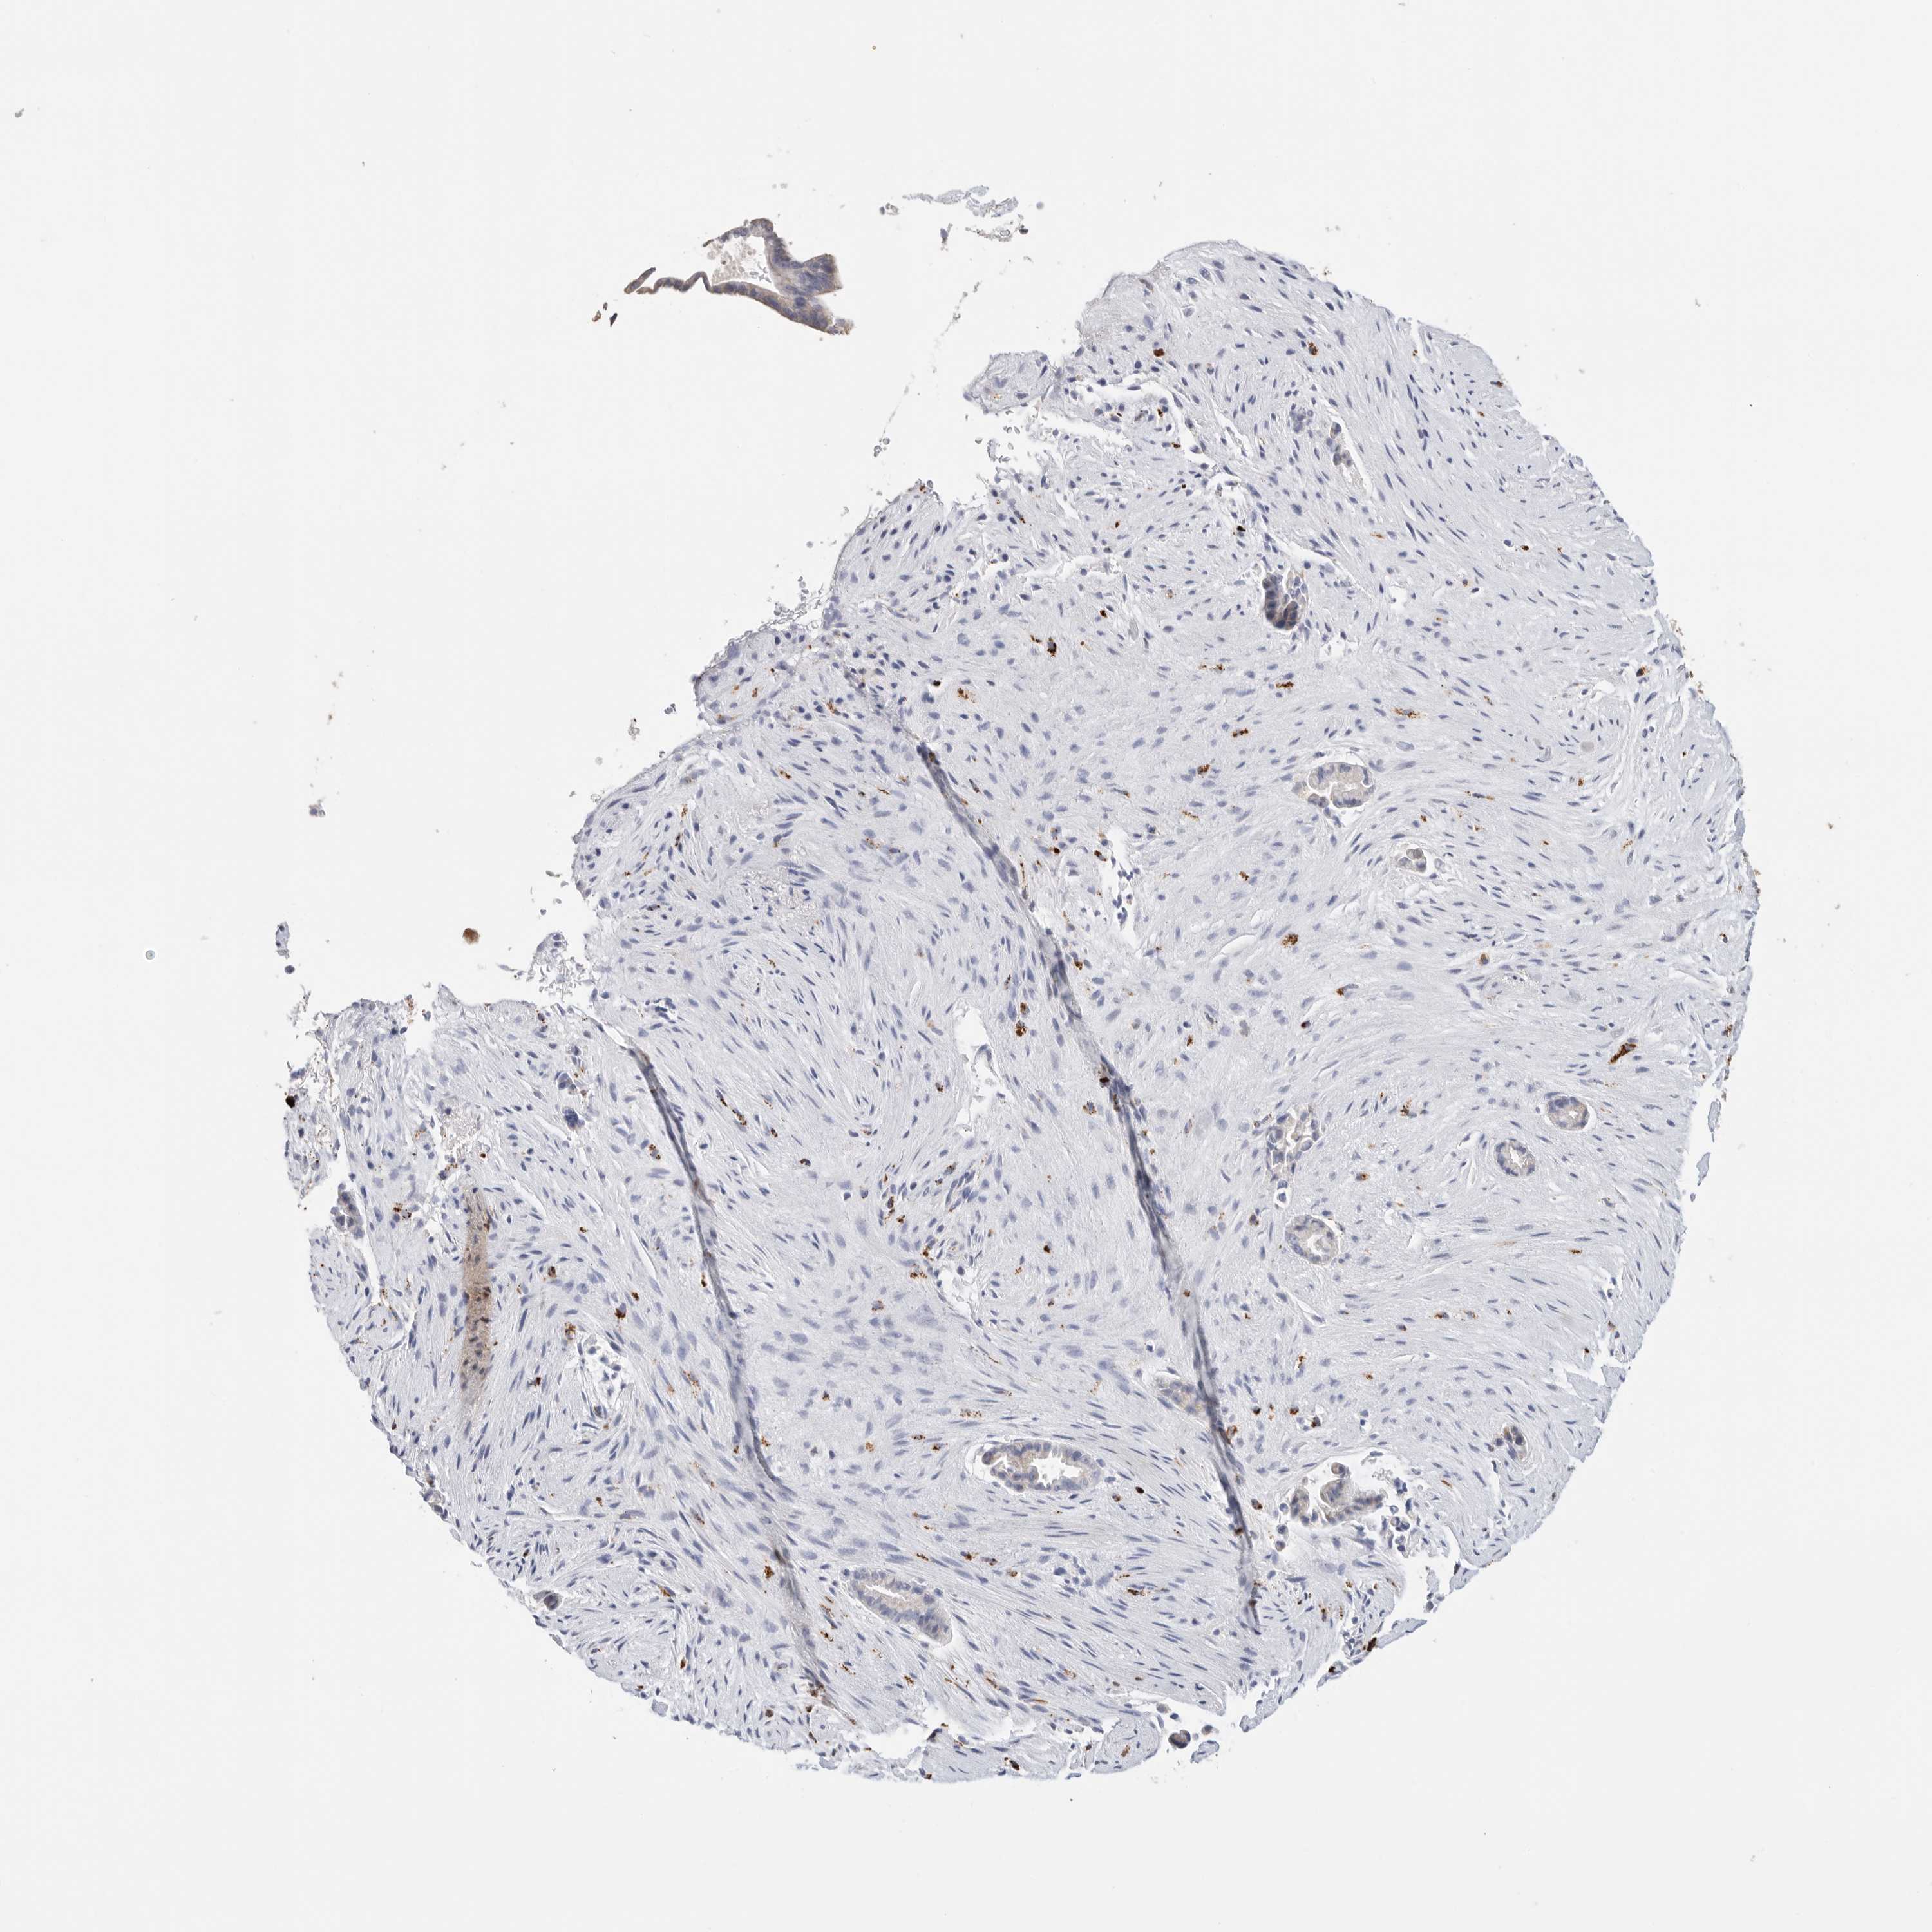

LIVER CANCER - Protein expressioni

A mouse-over function shows sample information and annotation data. Click on an image to view it in a full screen mode. Samples can be filtered based on level of antibody staining by selecting one or several of the following categories: high, medium, low and not detected. The assay and annotation is described here.

Note that samples used for immunohistochemistry by the Human Protein Atlas do not correspond to samples in the TCGA dataset.

Antibody stainingi

Antibody staining in the annotated cell types in the current human tissue is reported as not detected, low, medium, or high, based on conventional immunohistochemistry profiling in selected tissues. This score is based on the combination of the staining intensity and fraction of stained cells.

Each image is clickable and will lead to virtual microscopy that enables deeper exploration of all samples and also displays staining intensity scores, fraction scores and subcellular localization as well as patient and tissue information for each sample.

Antibody HPA025226

Antibody CAB019296

Staining

High

Medium

Low

Not detected

Intensity

Strong

Moderate

Weak

Negative

Quantity

>75%

75%-25%

<25%

None

Location

Nuclear

Cytoplasmic/membranous

Cytoplasmic/membranous,nuclear

Cholangiocarcinoma

Carcinoma, Hepatocellular, NOS